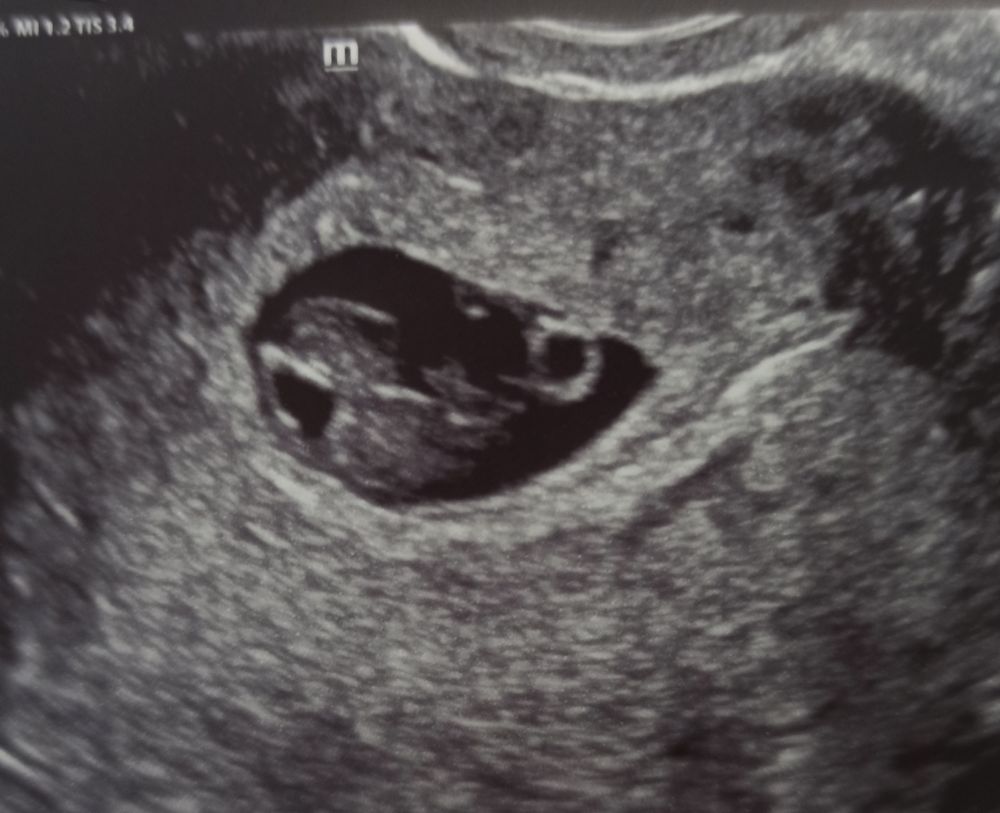

УЗИ на 41 дпо (7+6) ❤🤞🤞🤞

Сегодня 27 марта на 41 дпо (7+6) я сдала кровь в Инвитро на пол ребёнка, будет готов через 8 дней, где бы взять терпение, стараюсь не настраиваться на мальчика, чтобы не было сильно обидно. ХГЧ и прогестерон сдала для архива и сравнения с младшей дочкой, радует, что прогестерон стал чуть-чуть выше - 30,76 нг/мл, неделю назад был 26,74 нг/мл. По УЗИ всё хорошо слава Богу! 🙏🙏🙏 Киста ЖТ стала уменьшаться - 29*28 мм, неделю назад была 41*36 мм. Токсикоз так и не уходит, уже 3 недели мучаюсь, вымотана этой мутью, и ещё добавилась как 3-й день головная боль как мигрень, может от погоды, у нас ливень льëт 3-й день, слабость, головокружение, диарея сменилась запором, постоянно сушит во рту и горечь неприятная, от голода тошнит, после еды тяжесть и отрыжка. Хочу уже наконец-то наслаждаться беременностью, поскорей бы прошëл токсикоз.🙏🙏🙏